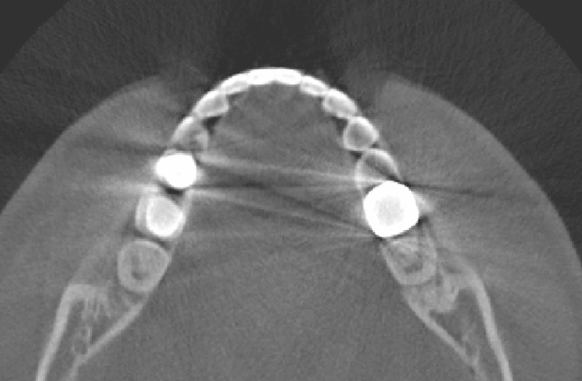

To validate our main results in the clinical CT case, we include CT image of one author’s teeth and mandible in Fig. 6. As shown in this figure, most streaking artifacts occur along the tangent line of boundary of metallic objects. Besides, due to scattering and/or noise effect, the streaking artifacts can occur between the metallic object and the bone, as described in the corollaries of this section.

Refer to caption

Figure 6: Illustration of streaking artifacts in clinical CT image. The presence of the streaking artifacts in the clinical CT image mostly agrees with the description in our main theorems and their corollaries.